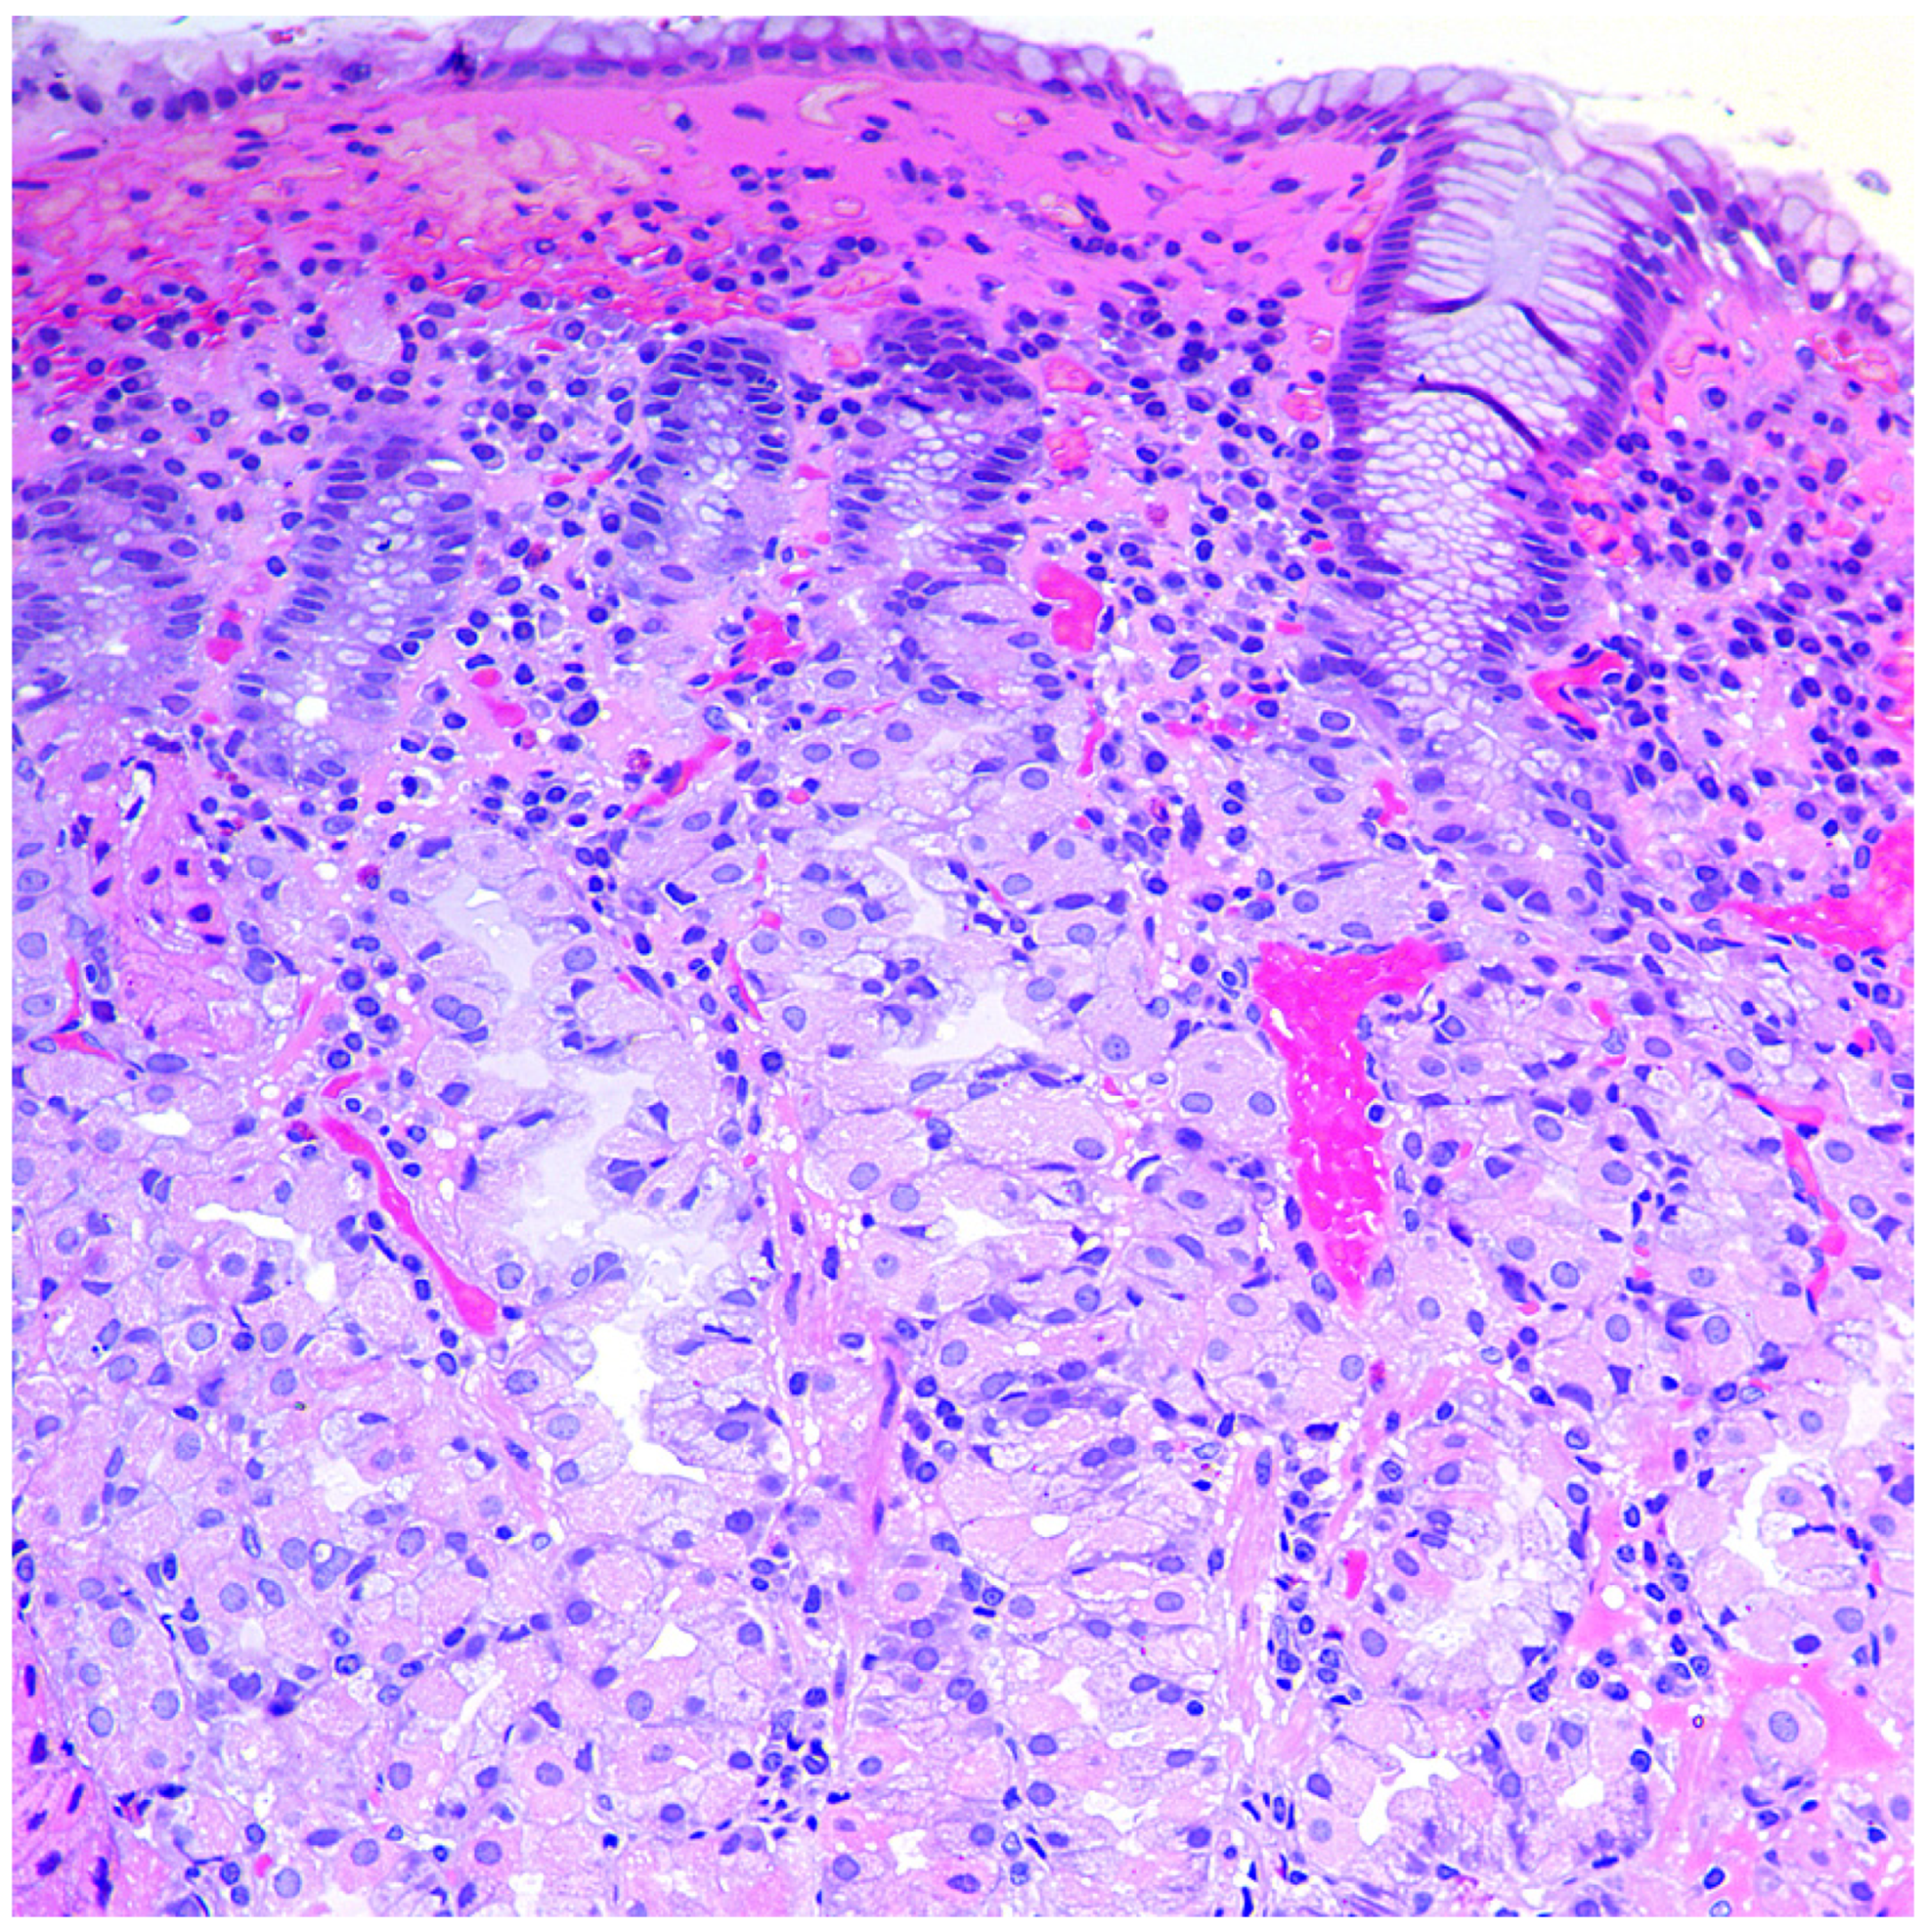

- Simple diffuse hyperplasia. This is characterized by a more than two-fold increase in the population of ECL cells. Diagnosis is difficult due to the lack of clear quantitative criteria. The diagnosis is poorly reproduced on biopsy material.

- Linear hyperplasia. The presence in one visual field of at least two groups of linearly located neuroendocrine cells, consisting of five or more cells. Usually, changes are diagnosed in the area of the neck glands (Figure 4).

- Micronodular hyperplasia. The presence of the cells’ cluster in contact with the basement membrane, but not exceeding the diameter of the gland, up to 150 μm in diameter, or a similar cluster located freely in the lamina propria of the mucous membrane.

- Adenomatous (adenomatoid) hyperplasia. The presence of an aggregate of five or more clusters (Figure 5).

- Neuroendocrine cells dysplasia. Merging clusters with diameters of more than 150 µm but less than 500 µm.